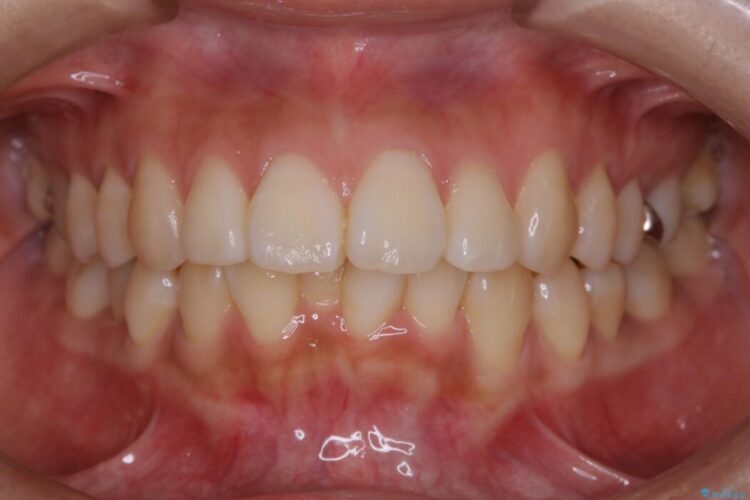

【20代女性】非抜歯でマウスピースの限界に挑戦する矯正治療

前歯を引っ込めるために非抜歯でのマウスピース矯正治療がしたいとの主訴で来院されました。

治療後について

患者様の意識も高く、しっかりとマウスピースを装着していただけたこともあり満足できる仕上がりとなりました。

本症例では最大量の移動もあり治療期間が掛かってしまいましたが、非抜歯でマウスピース矯正をしたいというご希望に応えることができました。